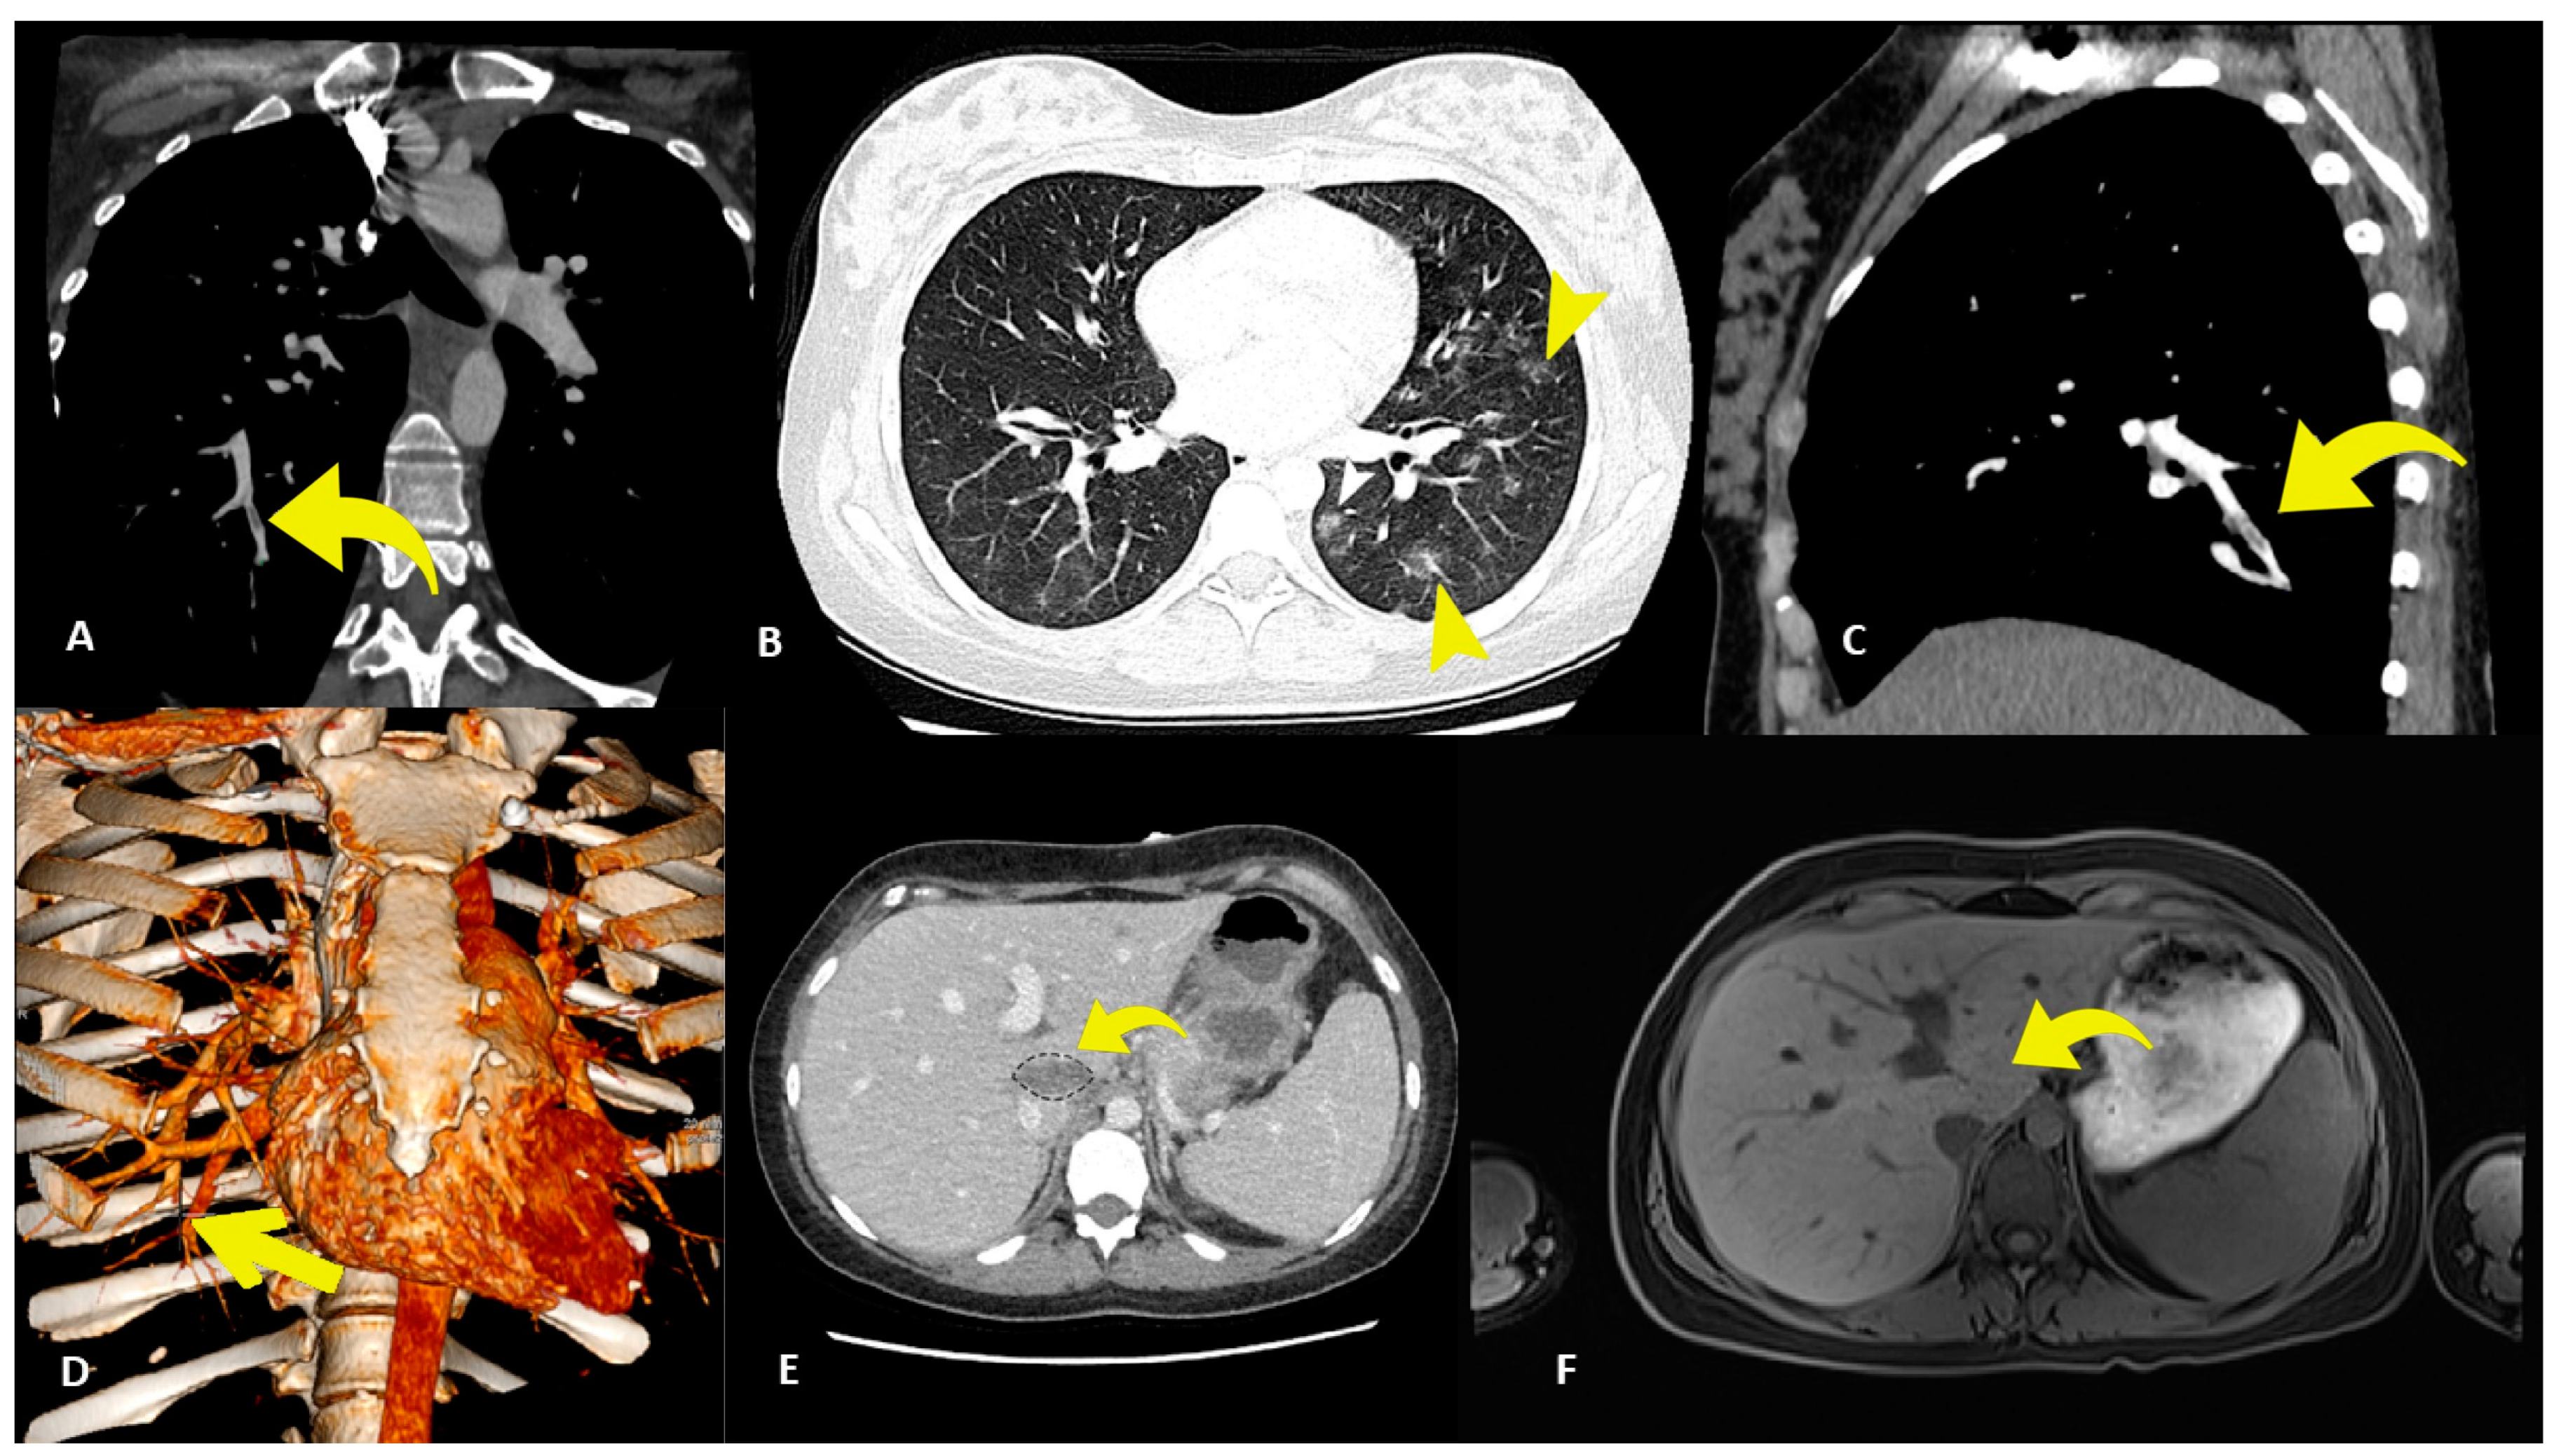

2. Case Presentation